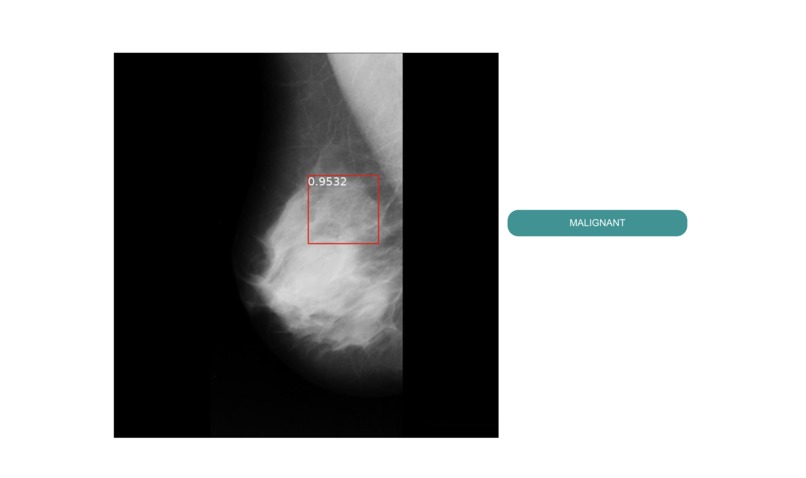

MediScan is web application powered by Deep Learning Models for predicting cancerous regions in breast mammograms. A user, for example a radiologist, would first select images to upload, a threshold value and then press submit. On submission, our backend will pass on the images to our deep learning models and will generate new images with bounding boxes if any are found. The bounding boxes will be clearly visible on the output images alongside with their probabilities.

We created a pipe for analysis of breast mammograms. We utilized 2 models. First an image goes through a Densenet model which predicts whether it is malignant or not. If malignant, the image is then passed into a FasterRCNN model which predicts cancerous regions with their corresponding probabilities. These models were both trained on DDSM dataset and were part of our research projects. We utilized PyTorch for training and inference of the models. We utilized Flask as the web framework for the web application.